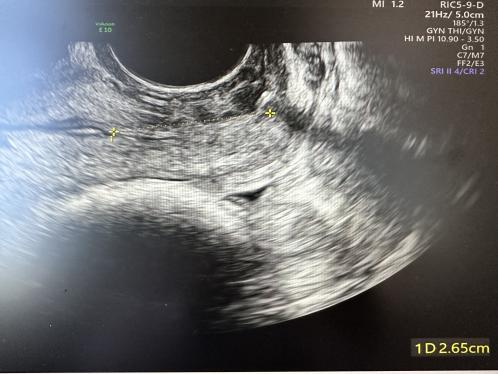

术后有效宫颈长度2.6cm

为什么要扩张宫颈孕妈不能承受之重:宫颈机能不全怎么办?_https://www.jmylbn.com_新闻资讯_第4张